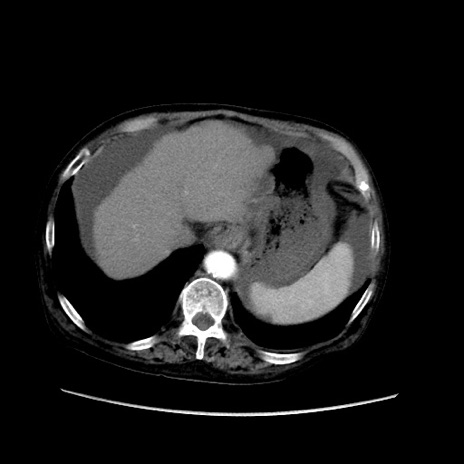

症例31(横断像)

【症例】80歳代 女性

【主訴】腹部膨満感

【現病歴】他院にて肝硬変にてフォロー中。1週間前から便秘、腹部膨満感、臍部腫瘤あり受診となる。

【既往歴】肝硬変

【身体所見】腹部膨隆あり、皮膚変化なし、疼痛なし。

【データ】WBC 4600、CRP 0.25